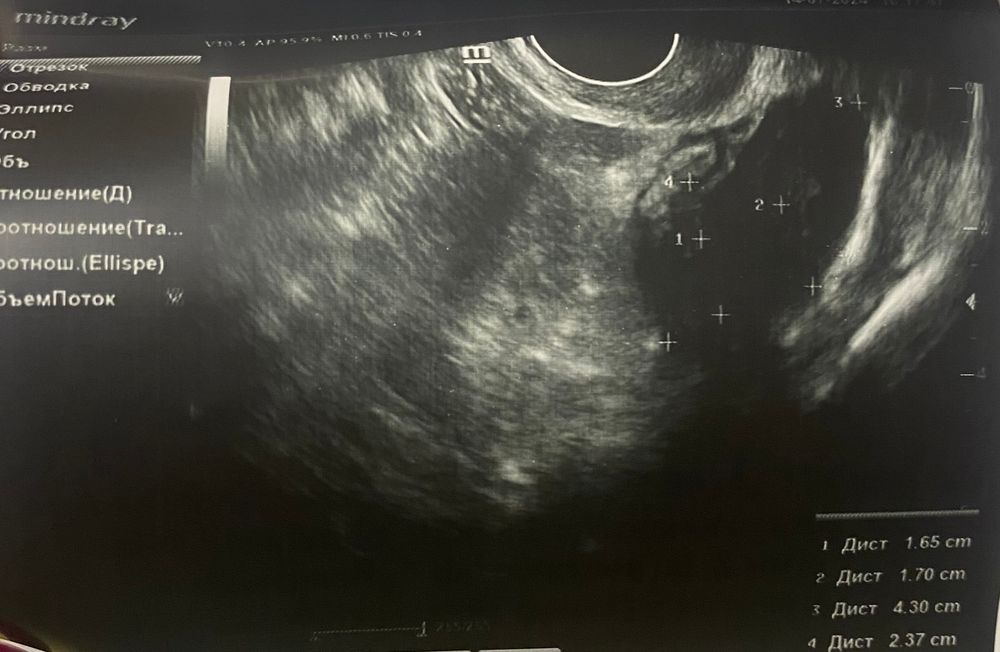

ЖТ или доминантный фолликул?

Как по мне, похож на фолликул 🤔 прям очень похож А ЖТ проверяют кровотоком вокруг, тут этого не увидеть. Но сколько я вот делала узи - это похоже на ДФ

Раз есть свободная жидкость значит О была! А значит это ЖТ

Понимаете, УЗИ это не тот метод исследования, где гадают по картинке. У ДФ или ЖТ есть еще косвенные признаки, как фазы эндометрия, наличник жидкости или отсутствия, кровотоки и вообще ракурсы. приложите протокол узи, и будет понятно.

Юлия , по протоколу это желтое тело, но у меня есть сомнения Изображение

Мари , на УЗИ вторичные признаки говорят за ЖТ. Если у Вас есть сомнения, или повторите УЗи, или сдайте прогестерон через 7-8 дней после предположительной овуляции.

Мари , просто у меня овуляция никогда не бывает раньше 17го дня, (обычно 19-21 дц), а тут на 13й день уже желтое тело

Больше напоминает ЖТ